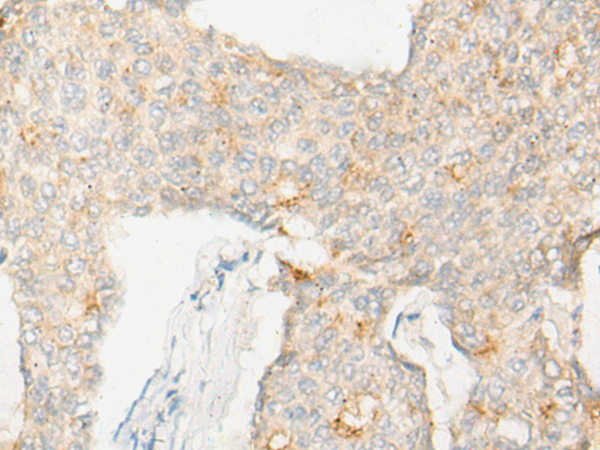

The image is immunohistochemistry of paraffin-embedded Human ovarian cancer tissue using 47071(DND1 Antibody) at dilution 1/20. (Original magnification: ?00)